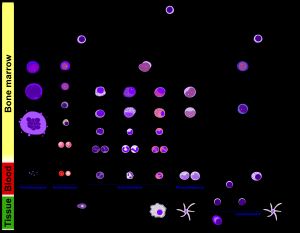

조혈은 혈액 세포가 생성되는 과정으로, 조혈모세포가 골수에서 분화하여 적혈구, 림프구, 과립구, 거핵구, 대식세포 등 다양한 혈구 세포를 생성한다. 조혈 과정은 적혈구 생성, 림프구 생성, 골수구 생성으로 나뉘며, 각 세포는 특정 계보를 따른다. 조혈모세포는 자기 재생 능력을 가지며, 성장 인자, 전사 인자, 미세 환경의 영향을 받아 세포의 운명이 결정된다. 조혈은 척추동물의 중요한 생명 과정 중 하나이며, 간, 비장 등 다른 기관에서도 일어날 수 있다.

2. 2. 세포 유형

모든 혈구세포는 3개의 계보로 나뉜다.[9][51]2. 3. 명명법

발생 중인 배아에서 혈액 생성은 난황낭 속 혈구세포 응집체인 혈도에서 시작된다. 발생이 진행됨에 따라 혈액은 비장, 간, 림프절에서 만들어진다. 골수가 발생하면, 대부분의 혈구세포가 골수에서 생성된다. 림프구의 성숙, 활성화, 증식은 비장, 흉선, 림프절에서 일어난다.